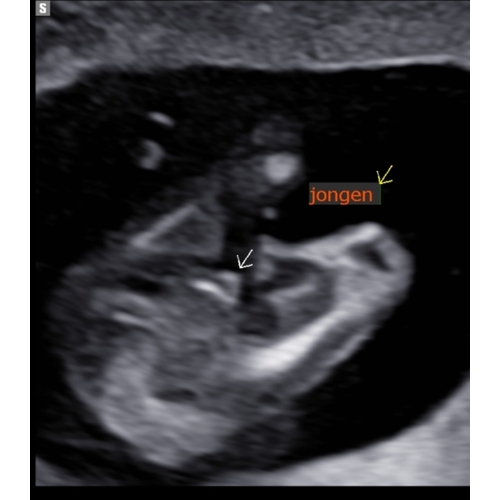

Met 15 weken 💙

Jongen

Ziet er zeker uit als een jongen haha. Je ziet duidelijk een piemel en ballen